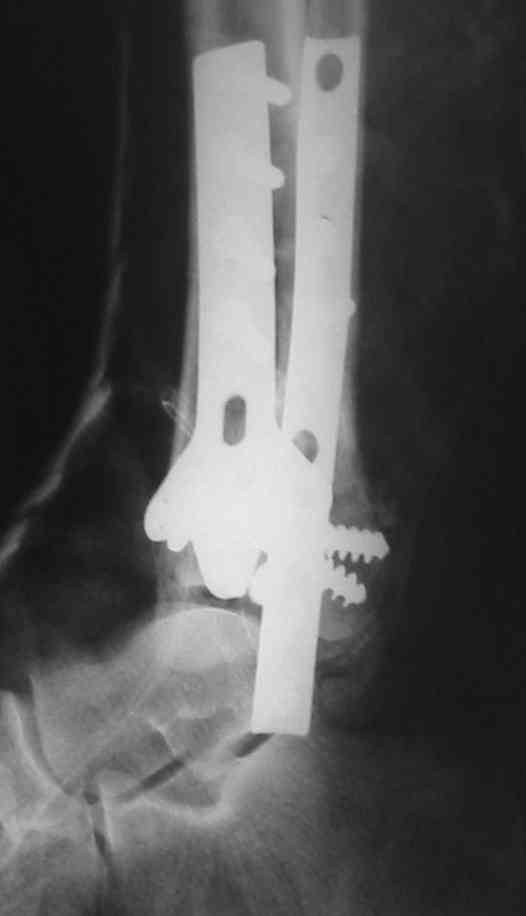

На рентгенограммах типичный перелом пилона по типу С-3. есть опыт до 100 открытых опреаций у нас в клинике. 20 примерно в год. Принцип один -все внутрисуставные переломы нуждаются в открытой репозиции и внутренней стабильной фиксации. При поступлении КТ не надо, так как получается только нагромождение костей. Истинной картины нет. Главное восстановить длину малоберцовой кости - это ключ к успеху. При поступлении меньше всего надо думать о сосудистых расстройствах, т.к. сама операция и репозиция даже сначала частичная даёт улучшение сосудитых нарушений. Причём очень быстро. Операция в 2этапа. При поступлении доступ позади наружной лодыжки, причём обязательно. После этого репозиция малоберцовой кости и фиксация пластиной 1/3 трубки под винт 3,5. Дренаж и любой аппарат наружной фиксации. Затем после спадения отёка на 5-7-10 день аппрат снимается и дугообразный разрез спереди от медиальной лодыжки 10-12 см. Главной чтобы расстояние между 1 и вторым разрезом было не меньше 7-8 см. Тогда не будет некрозов лоскутов. Таранная кость используется как матрица на неё укладываются отломки и фиксируются пицами. Ренг-контроль. Отломки лежат все отдельно, но ничего не высыпется. При переломах С-3 всегда нужна костная пластика (из крыла). Фиксация пластиной лист клевера простой или LCP. Гипс не нужен. Дренаж до 48 часов. Операция длится 3-4 часа обязательно без жгута. Посылаю примерно такой же случай.

Ja operiroval bolnogo po Vashemu, hotia sam ni ochen' ubezden' v itom, t.k. bolnoi otkazalsa na proch' ot ex.fix, ja emu sdelal ORIF + Kostnia plastika, snimky prelogiottsa,